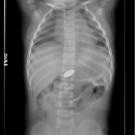

A 15-month-old boy was brought to an urgent care center by his father for suspected ingestion of a button battery.